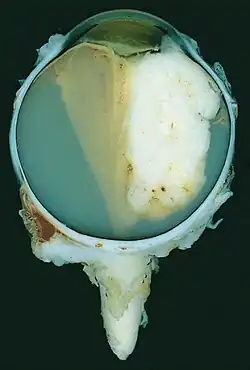

| A pathology specimen of a retinoblastoma tumor from an enucleated eye of a 3-year-old female | |

Large exophytic white tumor with foci of calcification producing total exudative retinal detachment -